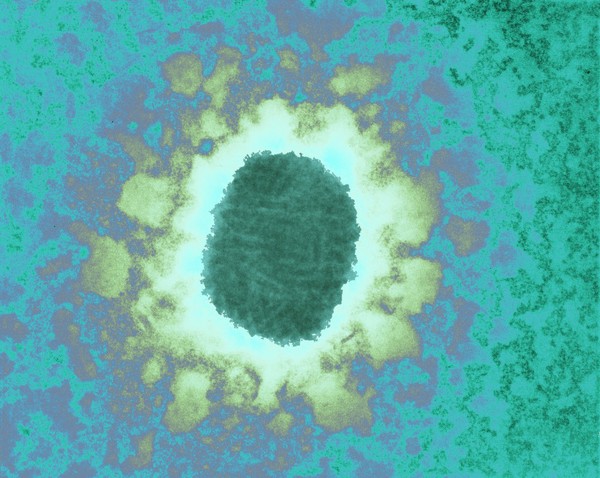

TEM of Molluscum virus

David Gregory & Debbie Marshall